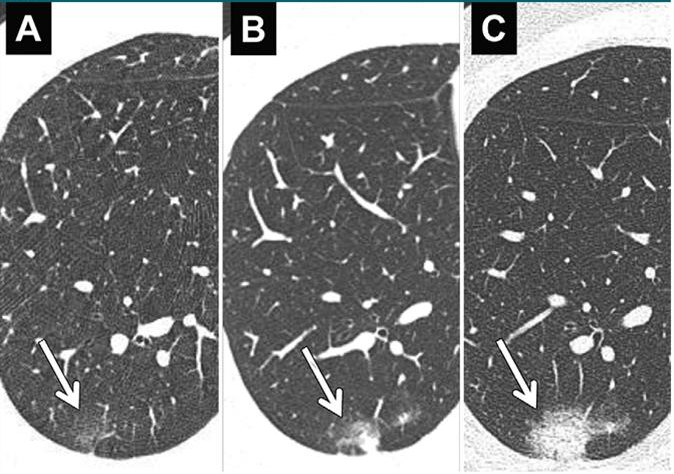

(图为肺结节在随访观察中的变化,其中A图为基线,B图为三个月后,C图为六个月后,该患者术后病理为浸润性腺癌)